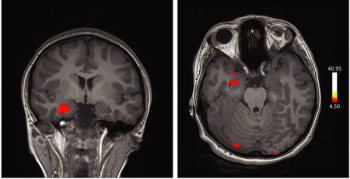

Images captured with fMRI in a case study reveal the role of the orbitofrontal cortex in patients infected with the virus who experience anosmia and ageusia.